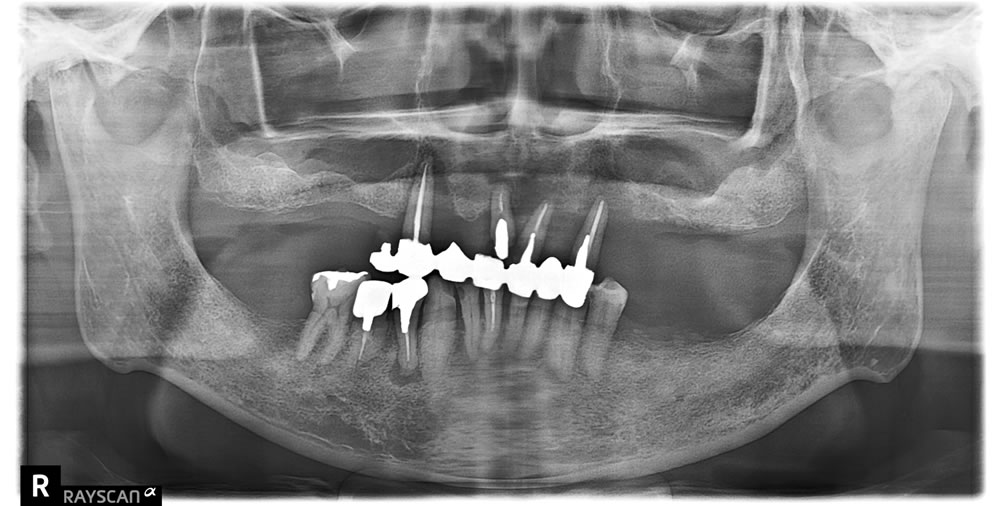

インプラント埋入手術

インプラント結合後に全顎精密仮歯の装着

インプラント手術から3ヵ月後、上下顎プロビジョナルレストレーション(仮歯)を装着しました。

- 上顎は総義歯

- 下顎左5・6番はインプラント

- 下顎その他はクラウン